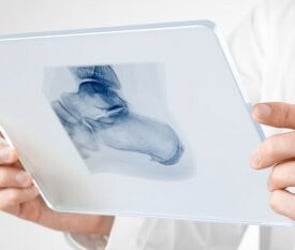

We provide the highest standard of podiatric care, utilising international gold standards of diagnosis and treatment.